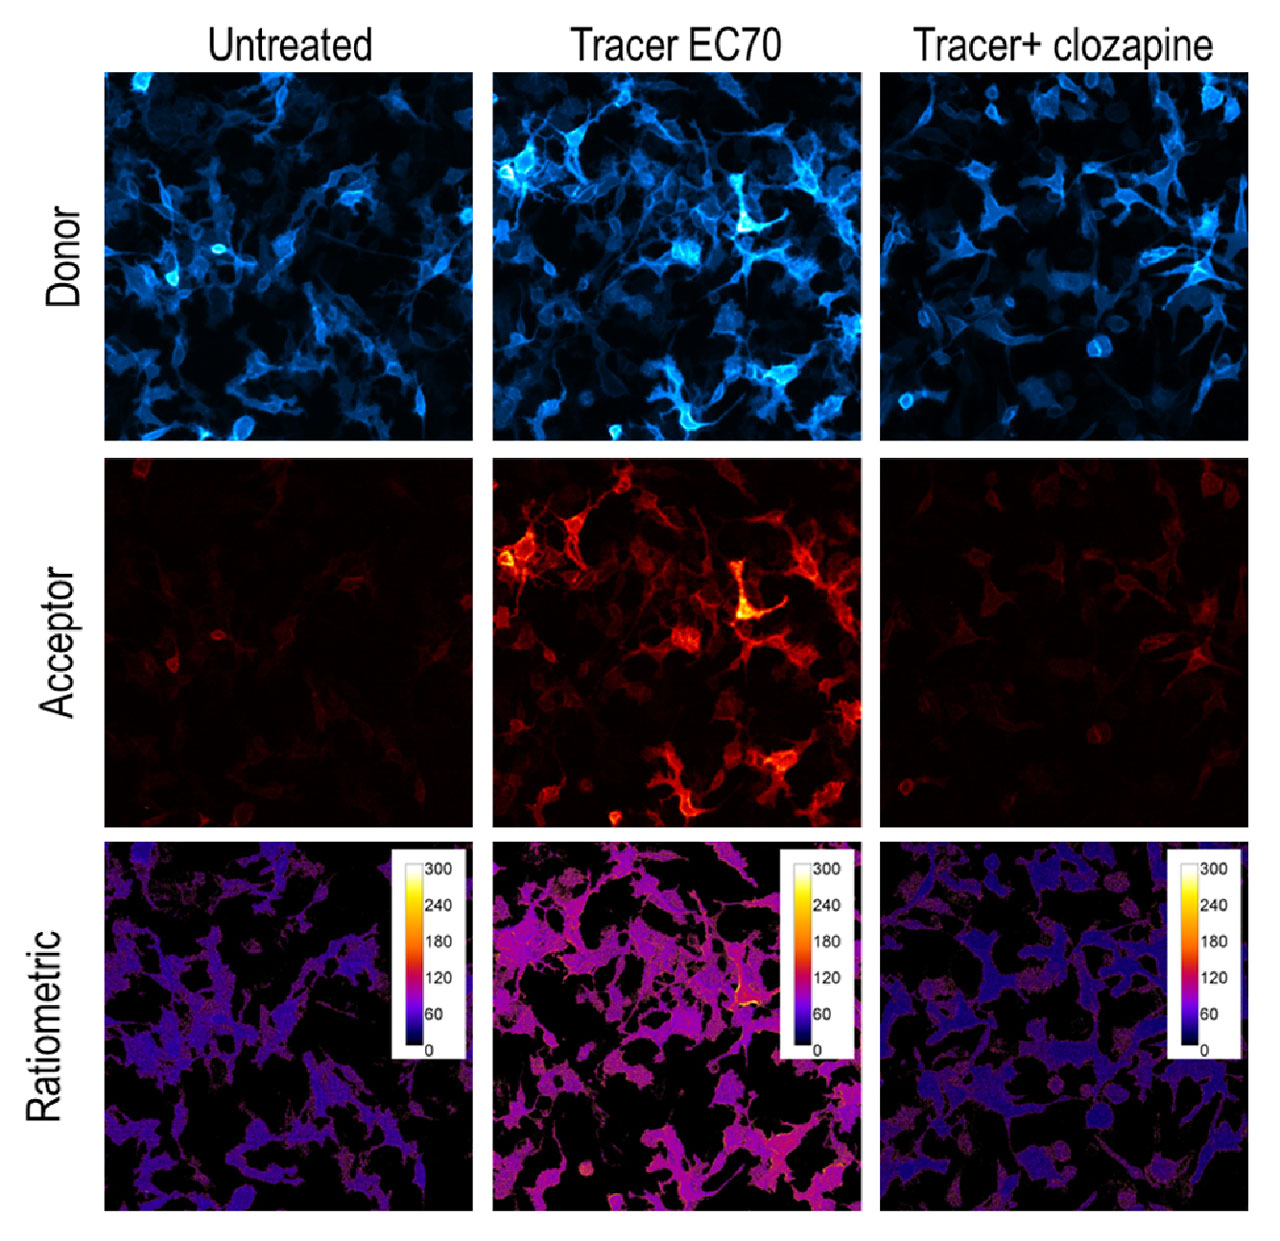

See the Data: Visualizing GPCR Target Engagement

GPCR Target Engagement for HTR2C Receptor using NanoBRET. Left Panel: HiBiT-5-HR2C target displacement using either clozapine or serotonin measured on the GloMax® Discover Microplate Reader. Right Panel: Donor and acceptor images captured on the GloMax® Galaxy Bioluminescence Imager. The donor channel was exposed for 60 seconds and acceptor channel was exposed for 120 seconds. Ratiometric images demonstrate BRET-ratio upon addition of Tracer EC70 alone or in combination with clozapine.